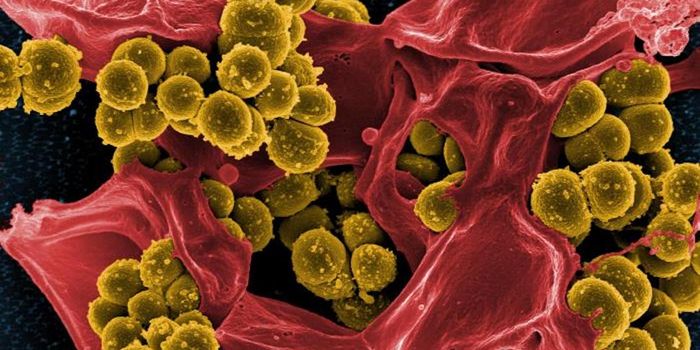

JAN 08, 2021MicrobiologyBacterial infections that can't be eliminated with standard drugs, caused by antibiotic-resistant bacteria, are consider ...